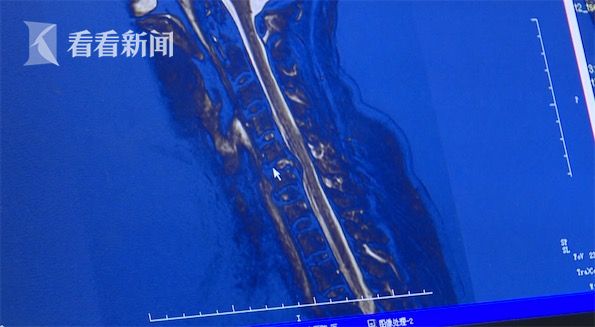

颈椎疼痛针灸推拿也不见好 当心这种罕见但严

640x427 - 35KB - JPEG

女子打完麻将突然上肢疼痛麻木 原是久坐患上

597x335 - 25KB - JPEG